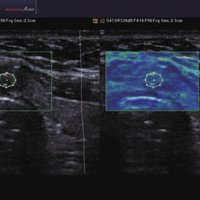

• FAD™, die Face Auto Detection, stellt das Gesicht eines Fötus besonders detailliert dar. Überflüssige Daten werden entfernt und ein besonders realistisches Bild gezeichnet.

• ElastoScan™ ermöglicht eine genauere Visualisierung von Tumoren und erfasst und dokumentiert Gewebesteifheiten.